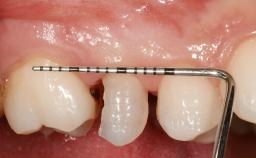

Early Placement of an Implant in a Maxillary Right Central Incisor Site

This 41-year-old female patient was referred to the clinic for the replacement of the right central incisor, since the tooth had developed a root fracture in the long axis that made extraction necessary. The healthy, non-smoking patient was first seen with the tooth still in place. A detailed Esthetic Risk Assessment was performed.The patient was worried about her dental esthetics and had high expectations for a successful treatment outcome from an esthetic point of view. The patient had a medium lip line that displayed parts of the gingiva in the anterior maxilla upon smile.

Mesio-Distal Space Symmetry +/- 1 mm of contra-lateral tooth

Soft Tissue Contour and Volume Slightly compromised